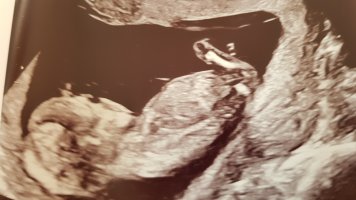

ja det vil jeg tro er en guttSniker fra mars. Her er min lille målt til 13+1. Er det en gutt?

Hurra!Det må kanskje ha vært den bakerste som er nub, for dette viste seg på OUL å være en guttja. ganske sikker på at dette er nub og at dette er en jente. barnet sitter nesten, men vinkelen er helt flat. det ville vært godt synelig 13+5 hvis det var en gutt.